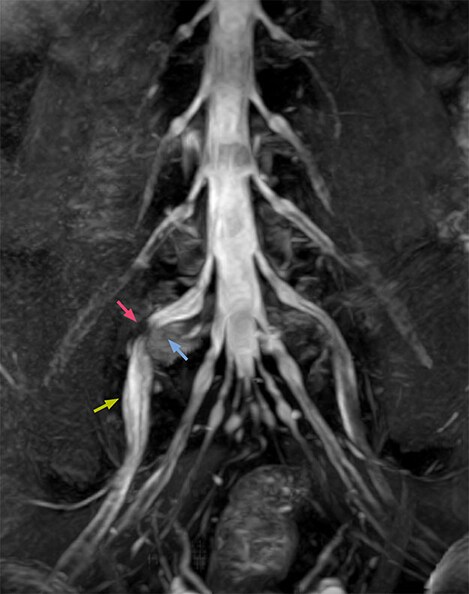

The L5/S1 (extraforaminal) far lateral lumbar disc herniation (blue) is seen in the images, as well as identification of the narrowing point in the right nerve root (pink) and edematous change on the proximal and distal part (green).

After surgery for right L5 radiculopathy, the symptoms of the patient were significantly improved.

MRI neurography of right L5 radiculopathy

Clinical case: NerveVIEW imaging of right L5 radiculopathy

After a previous successful surgical operation to treat a lumbar disk hernia, this patient still had strong numbness from right hip to the lower extremity. The patient then underwent MRI with 3D NerveVIEW on Achieva 3.0T dStream. NerveVIEW voxels 0.99 x 1.07 x 1.25 mm rec, 5:47 min.

These NerveVIEW images helped to identify the cause of pain, being L5/S1 (extraforaminal) far lateral lumbar disc herniation. Based on these findings, the patient underwent a second surgery, after which symptoms significantly improved.

Nerve VIEW imaging of right L5 radiculopathy